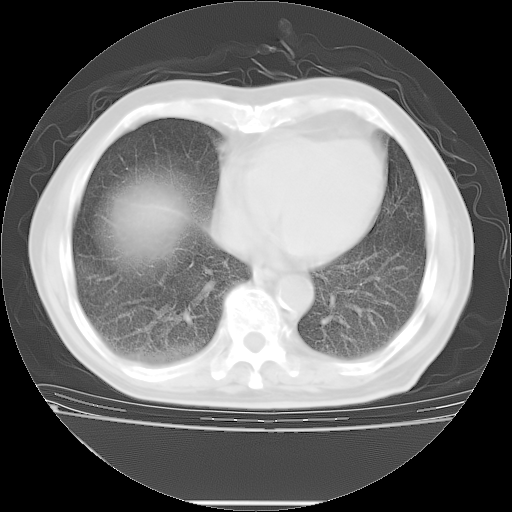

今天复查肺部CT,发现双肺广泛磨玻璃样改变。所以我把3月19日和5月9日相隔50天的肺部CT上传。请大家会诊。

2009年3月19日肺部CT片。

5月9日肺部CT(在4月27日齐鲁医院肺部CT描述部分肺组织磨玻璃样改变,12天后肺组织广泛磨玻璃样改变)